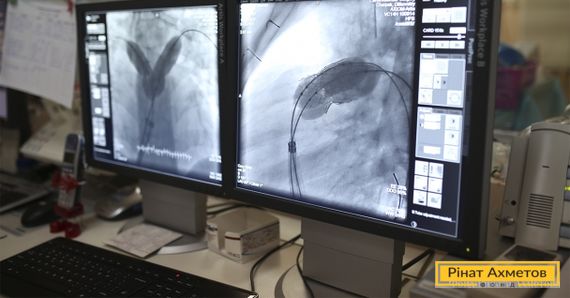

Ендоваскулярний метод означає, що операція проводиться без розрізу грудної клітки. Але для цього потрібен оклюдер. Це спіраль розміром шість міліметрів. Через невеликий розріз на стегні й артерію оклюдер із потоком крові проникає в проблемне місце прямо в серце. Розкриваючись подібно до парасольки, оклюдер закриває протоку і згодом заростає м’язовою тканиною.